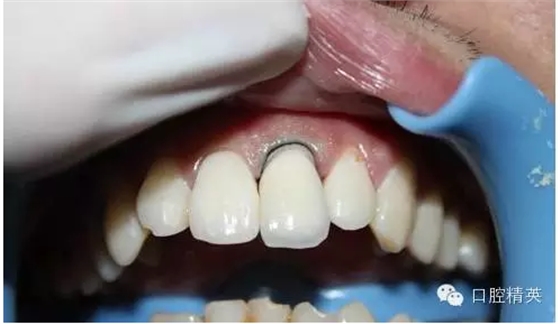

一年輕小伙,在打籃球中,被隊(duì)友打斷門牙,來(lái)本診所時(shí)已經(jīng)露髓,局麻拔髓后,行RCT。后因經(jīng)濟(jì)關(guān)系,擬鈷鉻樁加鈷鉻烤瓷冠修復(fù),備牙后才留照片:

1:牙根,備牙后,

2:唇側(cè)觀,

3:鈷鉻金屬樁黏結(jié)后